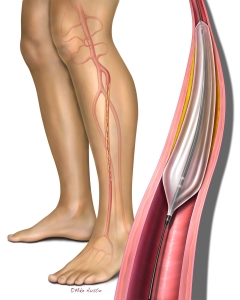

Welcome to my Patient and Professional Marketing page, where I harness the power of anatomical illustrations to educate and empower both patients and medical professionals. My unique approach combines artistry and education to convey complex surgical procedures and the utilization of medical devices in an easily understandable manner.